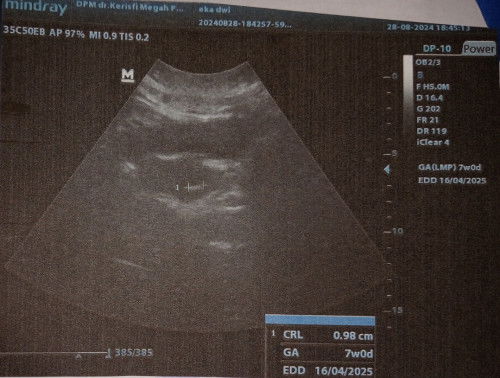

Bunda, ini kan uk saya masuk minggu ke-7 sesuai HPHT. Di tanggal 12 Agustus kemarin sudah check ke bidan katanya perut bagian bawah udah tegang, dan dikasih asam folat. Terus disuruh kontrol lagi 1bulan langsung disuruh USG.. Menurut bunda disini, lebih baik nurut sama bidannya atau saya USG di minggu minggu ini. Kalau nurut kata bidan, waktu USG perkiraan di uk 9w. #Sharing_dong_Bund